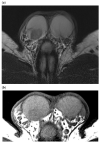

Pre-operative testicular tumor characterization is a challenge for radiologists and urologists. New data concerning imaging approaches or immunochemistry markers improve the management of patients presenting with a testicular tumor, sometimes avoiding radical orchiectomy. In the past 20 years, imaging modalities, especially ultrasound (US) and magnetic resonance imaging (MRI), improved, allowing for great progress in lesion characterization. Leydig cell tumors (LCT) are rare testicular tumors developing from the stromal tissue, with relatively scarce literature, as most of the studies focus on the much more frequent germ cell tumors. However, with the increase in testicular sonography numbers, the incidence of LCT appears much higher than expected, with some studies reporting up to 22% of small testicular nodules. Multimodal ultrasound using Doppler, Elastography, or injection of contrast media can provide crucial arguments to differentiate LCT from germ cell tumors. Multiparametric MRI is a second intention exam, but it allows for extraction of quantifiable data to assess the diagnosis of LCT. The aims of this article are to review the latest data regarding LCT imaging features, using multimodal ultrasound and multiparametric MRI, and to focus on the peculiar aspect of the testis of patients with Klinefelter's syndrome. The possibility of an LCT should be raised in front of a small hypoechoic tumor with a marked corbelling hypervascularization in an otherwise normal testicular pulp. Ultrasonographic modules, such as ultrasensitive Doppler, contrast-enhanced ultrasonography, or elastography, can be used to reinforce the suspicion of LCT. MRI provides objective data regarding vascularization and enhancement kinetics.